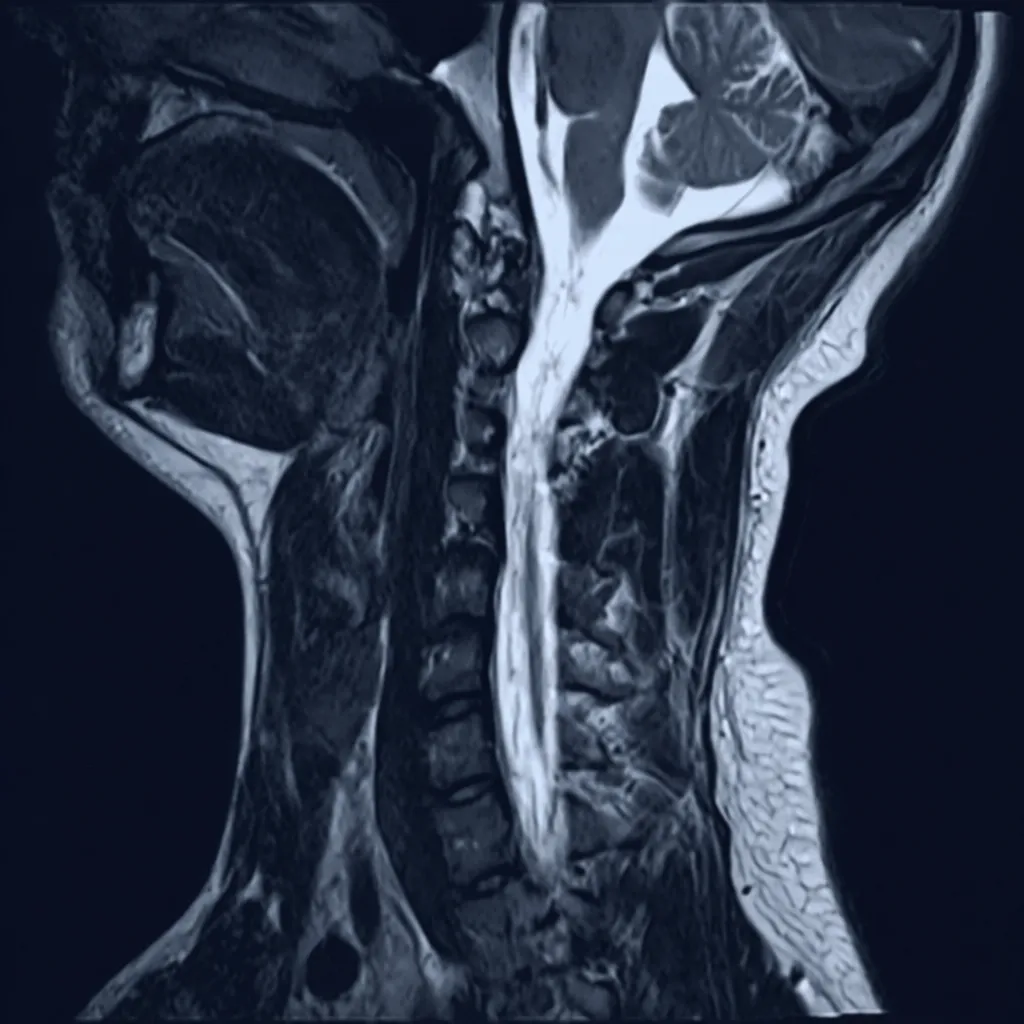

Spinal Instability & Symptomatic Disk, Joints and Ligaments

Platform identifies imaging findings related to spinal instability, symptomatic disc abnormalities, facet joint changes, and ligamentous injuries for physician review and clinical correlation.

AI-Driven Clinical Insight

Multi-Level Spine Analysis Example

Imaging shows findings consistent with instability at L4/5 and L5/S1 following prior percutaneous disc procedure. Board-certified physician review recommended for treatment planning.